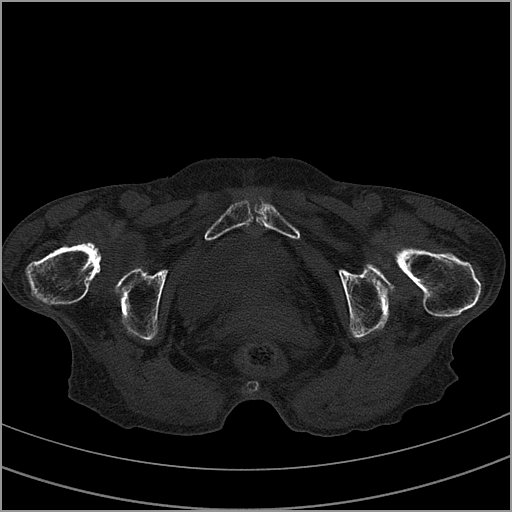

以下是引用老爱克斯新网客在2009-2-3 19:42:00的发言:[br]右侧髋臼及右侧股骨头可见明显骨质破坏,以溶骨性破坏为主,无明显硬化,髋关节间隙变窄,周围软组织明显肿胀,密度不均,脂肪间隙消失。[br] 诊断:右侧髋关节感染性病变,右侧髋关节结核的可能大。[br] 鉴别诊断:1.股骨头缺血坏死,单纯股骨头缺血坏死病例不会累积髋臼骨破坏。2。退行性关节炎,以骨质增生为主,伴有关节面硬化,骨质破坏呈多发小囊状破坏为主,其周围可见硬化环。3.股骨头缺血坏死晚期(第四期)骨质破坏可伴髋关节退行性变,可有骨质增生,但此时骨破坏以股骨头破坏为主,不应该伴有髋臼骨质破坏,因为股骨头的骨破坏是因血运中断,而没有髋臼的血运中断,又没有细菌的感染,怎么能造成髋臼的骨破坏呢。